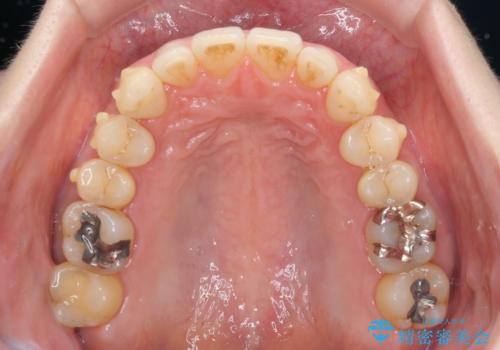

八重歯のインビザライン矯正治療

- 下顎の八重歯と、上下のクロスバイトを気にして来院された患者様です。

インビザラインを用い、下顎全体の後方移動、IPR(歯と歯の間を削る)と歯列全体を拡大させることで、歯並びを整えていくこととしました。

奥に位置していた上の前歯が下の前歯を乗り越える際、奥歯でものを咬むことができず、辛い時期が続きました。